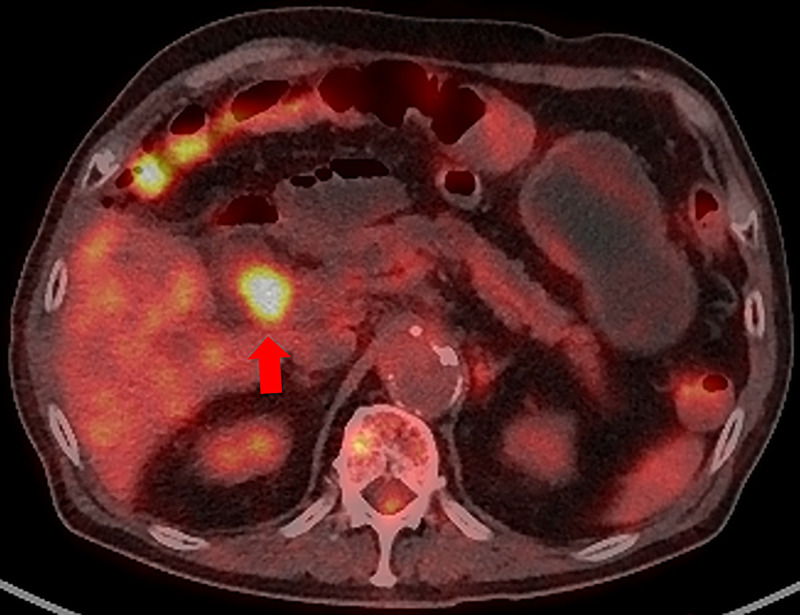

Successful EUS-guided fine-needle biopsy using a forward-viewing echoendoscope for local recurrence at the choledochojejunal anastomotic site 13 years after pancreaticoduodenectomy for cholangiocarcinoma.

胰十二指肠切除术治疗胆管癌13年后胆肠吻合口局部复发,超声引导下前视超声内镜下细针活检成功。